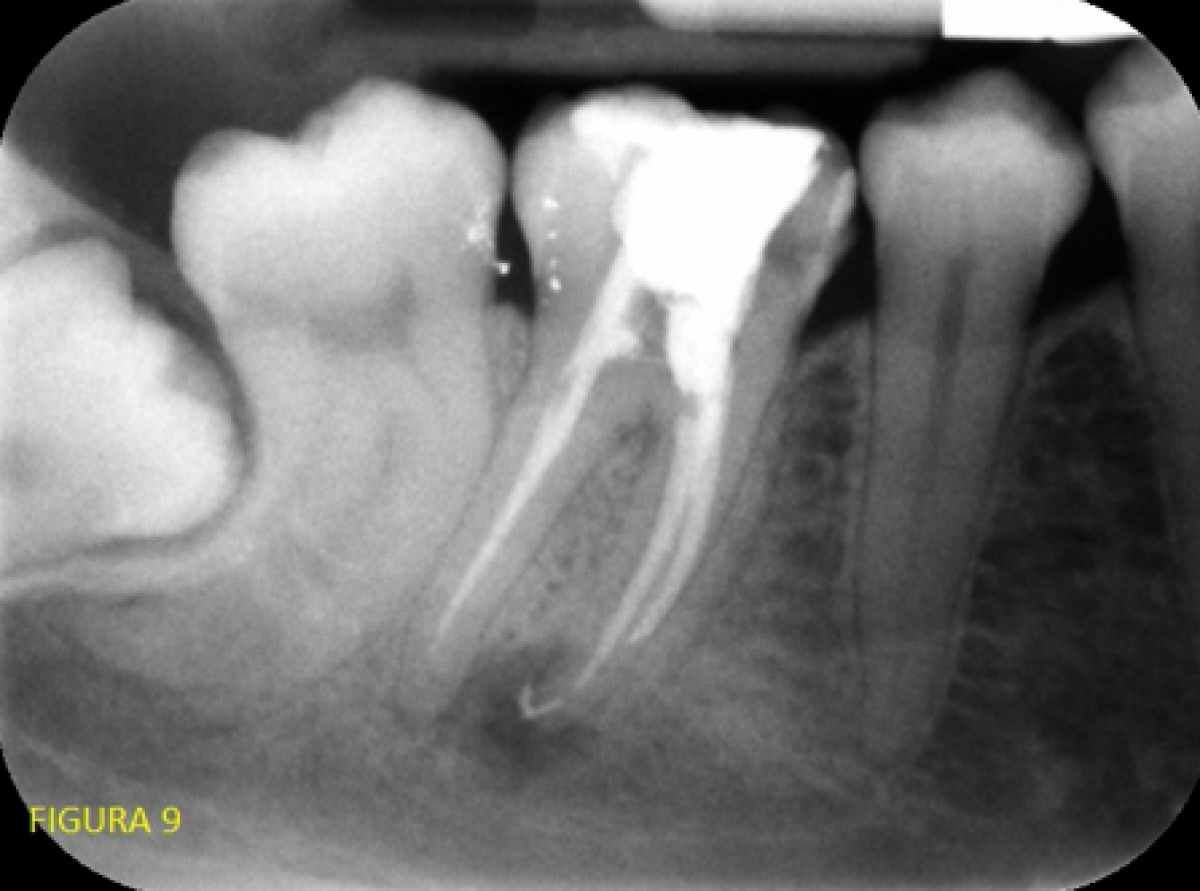

In the other two we insisted relatively little in trying to get to the apex, deeming it easier to create a false path than go through a canal so small as to be undetectable with a 68-micron CBCT examination. Intraoral X-ray at the end of retreatment (fig. 9).